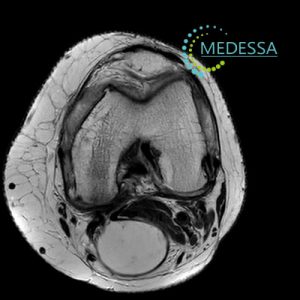

МРТ колінного суглоба – Кіста Бейкера або бурсит Бейкера

Кіста Бейкера, також відома як кіста синовіальної оболонки або бурсит Бекера, є аномалією, пов’язаною з суглобом, найчастіше з колінним суглобом. Ця кіста формується внаслідок накопичення суглобової рідини в задній частині коліна, утворюючи мішок або кісту.

МРТ надає докладні зображення м’яких тканин, кісток та суглобів, що дозволяє лікарям побачити структурні зміни в колінному суглобі, включаючи кісти, пошкодження хряща, запалення та інші аномалії.

5. Контроль ефективності лікування:

Після початку лікування МРТ може використовуватися для відстеження змін у колінному суглобі та оцінки ефективності застосовуваних методів лікування.

Загалом МРТ відіграє важливу роль у діагностиці та лікуванні колінних проблем, таких як кіста Бекера, надаючи детальну інформацію, яка допомагає лікарям приймати поінформовані рішення про лікування пацієнтів.